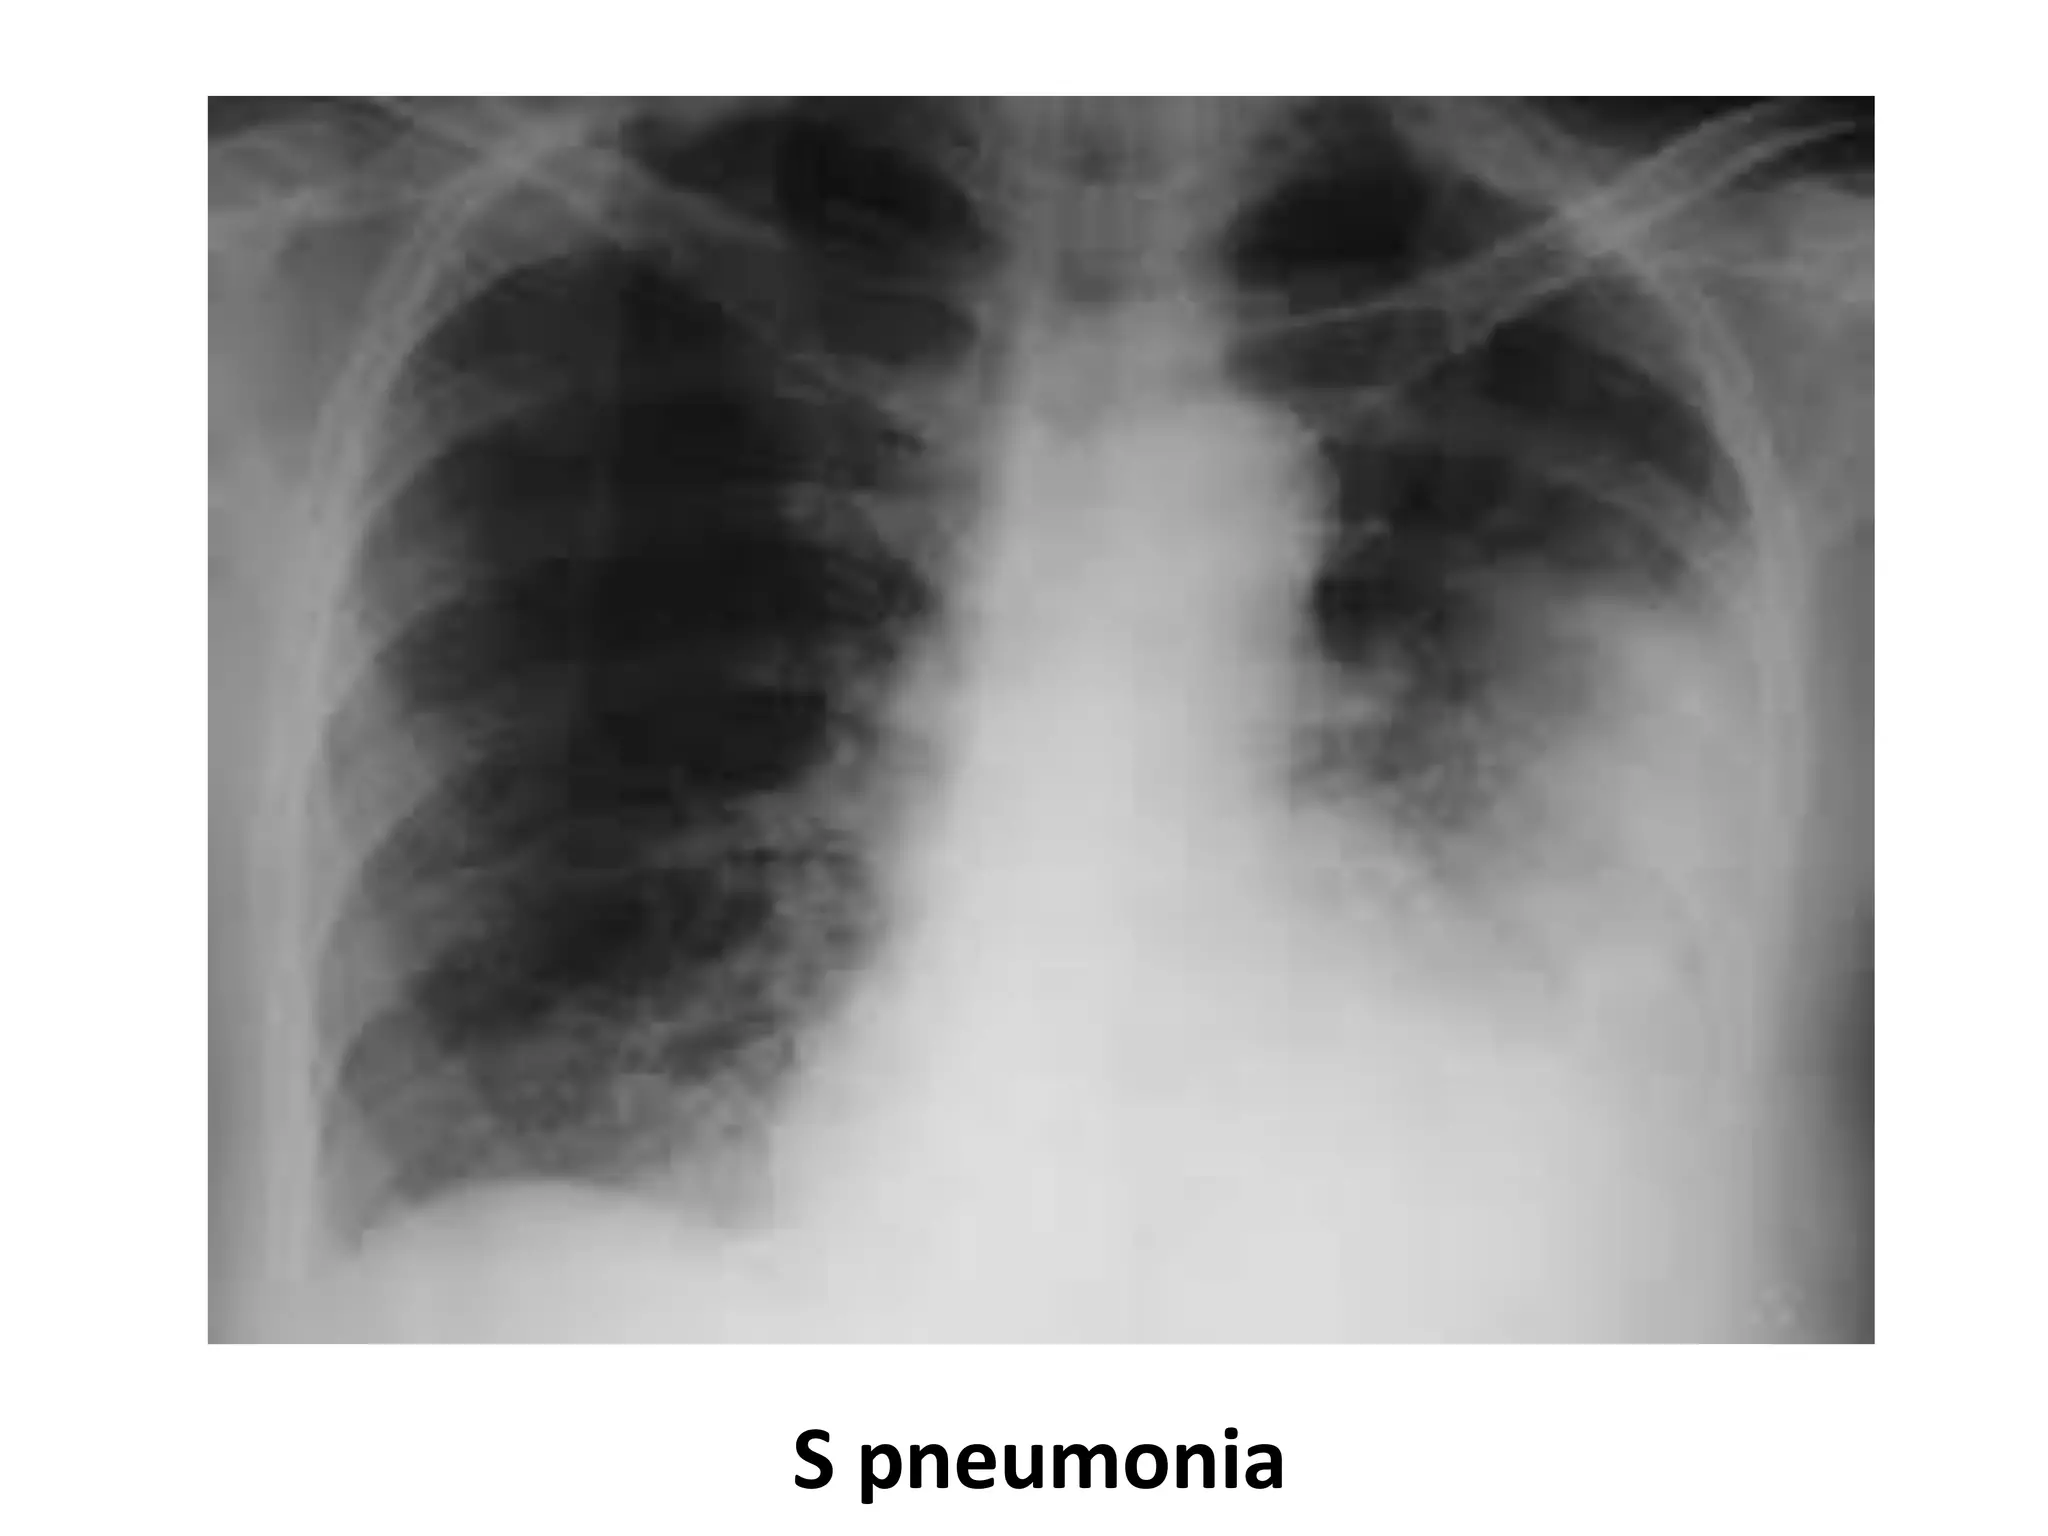

S pneumonia